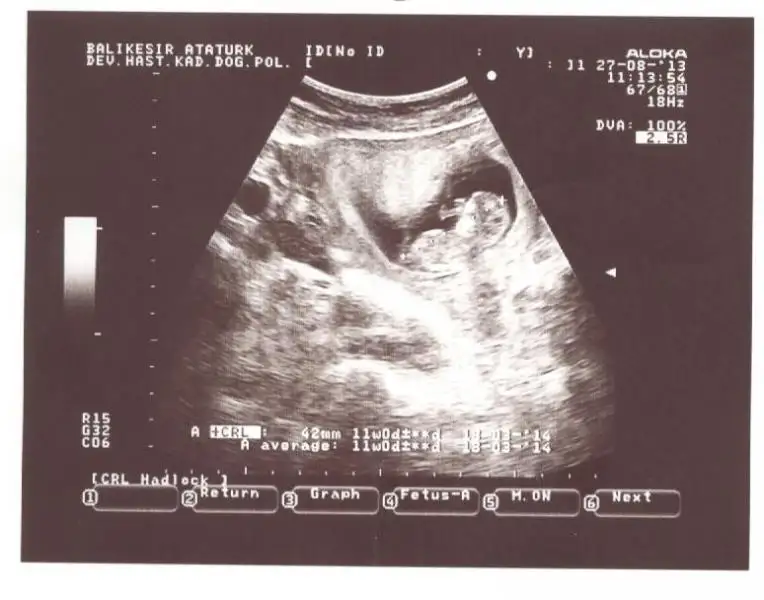

kızlar benim resimlerede bi yorum yapın ne acaba?ben anlayamadım.çabuk yazın çok merak ediyorum![]()

hayret bu resme gore kiz dr erkek demis gerci resim tamda net degil allhim tamamina erdirsin